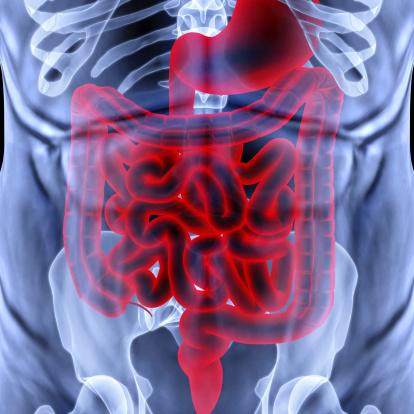

Twisted bowel (volvulus) in adults: How the bowels twist and how to treat it

Having a twisted bowel is like having a twist or loop that results in the obstruction of fecal matter moving through the intestines. The medical term for the condition is volvulus, which can occur in the small or large intestine. It may be referred to as small bowel volvulus or colonic volvulus, respectively. Where the ...click here to read more